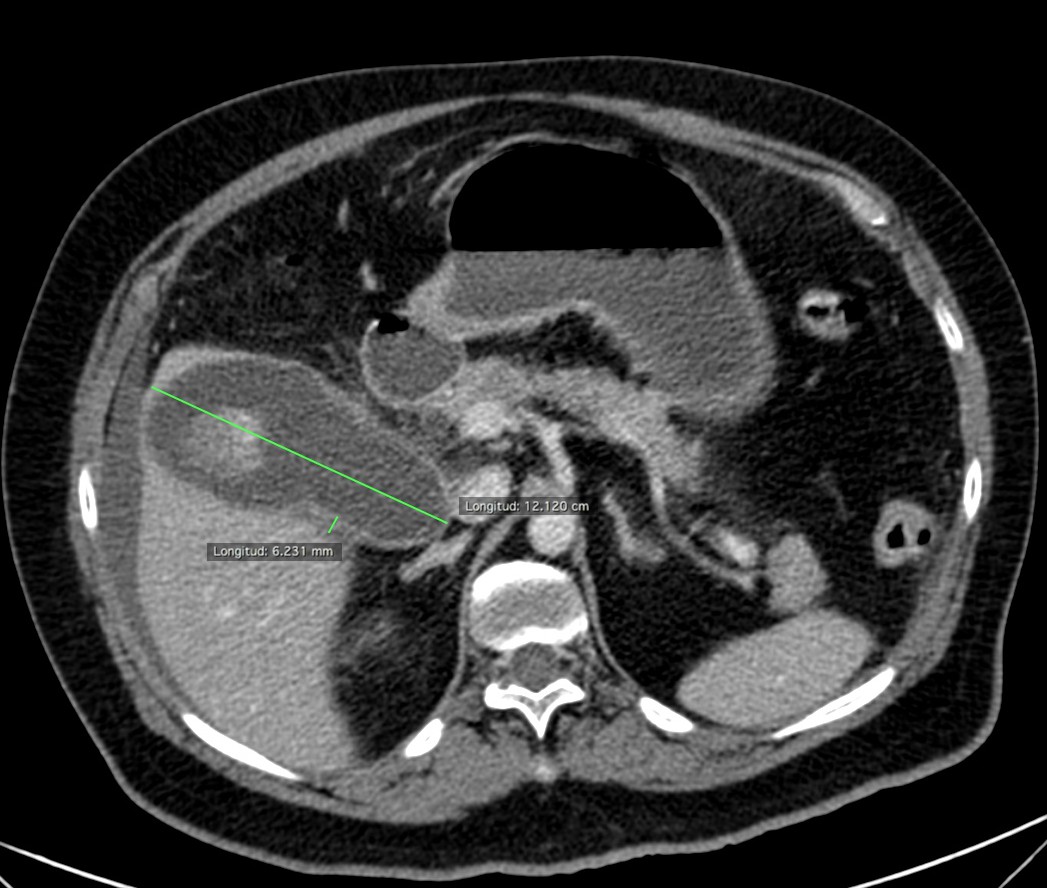

Se realizó posteriormente TC abdominal por mala evolución del paciente:

– La TC se reserva para pacientes con dudas diagnósticas o con discrepancia clínico ecográfica. Se obervarán los mismos hallazgos que en la ecografía, además del aumento de densidad de la pared de la vesícula, del parénquima hepático o especialmente la presencia de otras complicaciones.